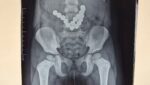

Маалыматка ылайык, бейтап 3 күн аралыгында улам-улам кусуп жаткандыгына байланыштуу райондук ооруканага кайрылып, рентген текшерүүнүн жыйынтыгында ичегилерде бир нече тизилген бөтөн зат аныкталкан.

Тажрыйбалуу хирургдарынын бригадасы бейтапка шашылыш операция жасап, 17 даана магнит ичегилерден толук алынган. Учурда бейтаптын абалы туруктуу, тиешелүү дарылоо жана көзөмөл жүргүзүлүп жатат.